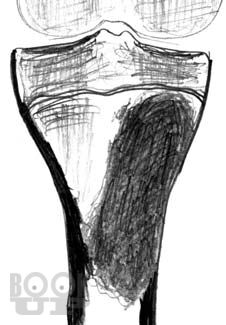

Рентгенологические и ультразвуковые исследования при заболеваниях суставов

Семизоров А. Н. Рентгенологические и ультразвуковые исследования при заболеваниях суставов : Пособие для врачей / А. Н. Семизоров, С. В. Романов. - М. : Видар-М, 2008. - 216 c. - ISBN 9785884291140. - Текст : электронный // ЭБС "Букап" : [сайт]. - URL : https://www.books-up.ru/ru/book/rentgenologicheskie-i-ultrazvukovye-issledovaniya-pri-zabolevaniyah-sustavov-9194384/ (дата обращения: 23.05.2026). - Режим доступа : по подписке.

Предлагаемая книга является дальнейшим развитием вышедшего ранее пособия «Ретнгенологическое и ультразвуковое исследование при заболеваниях

суставов».

Иллюстративная часть материала дополнена рентгенограммами, расширен

и углублен текст. В книге изложены основы рентгенологической и ультразвуко

вой диагностики дегенеративнодистрофических, воспалительных и других

заболеваний суставов. Представлены особенности диагностики при наиболее

часто встречающихся в клинической практике заболеваниях суставов.

Пособие рассчитано на рентгенологов, врачей УЗИ, ортопедов и врачей других специальностей.